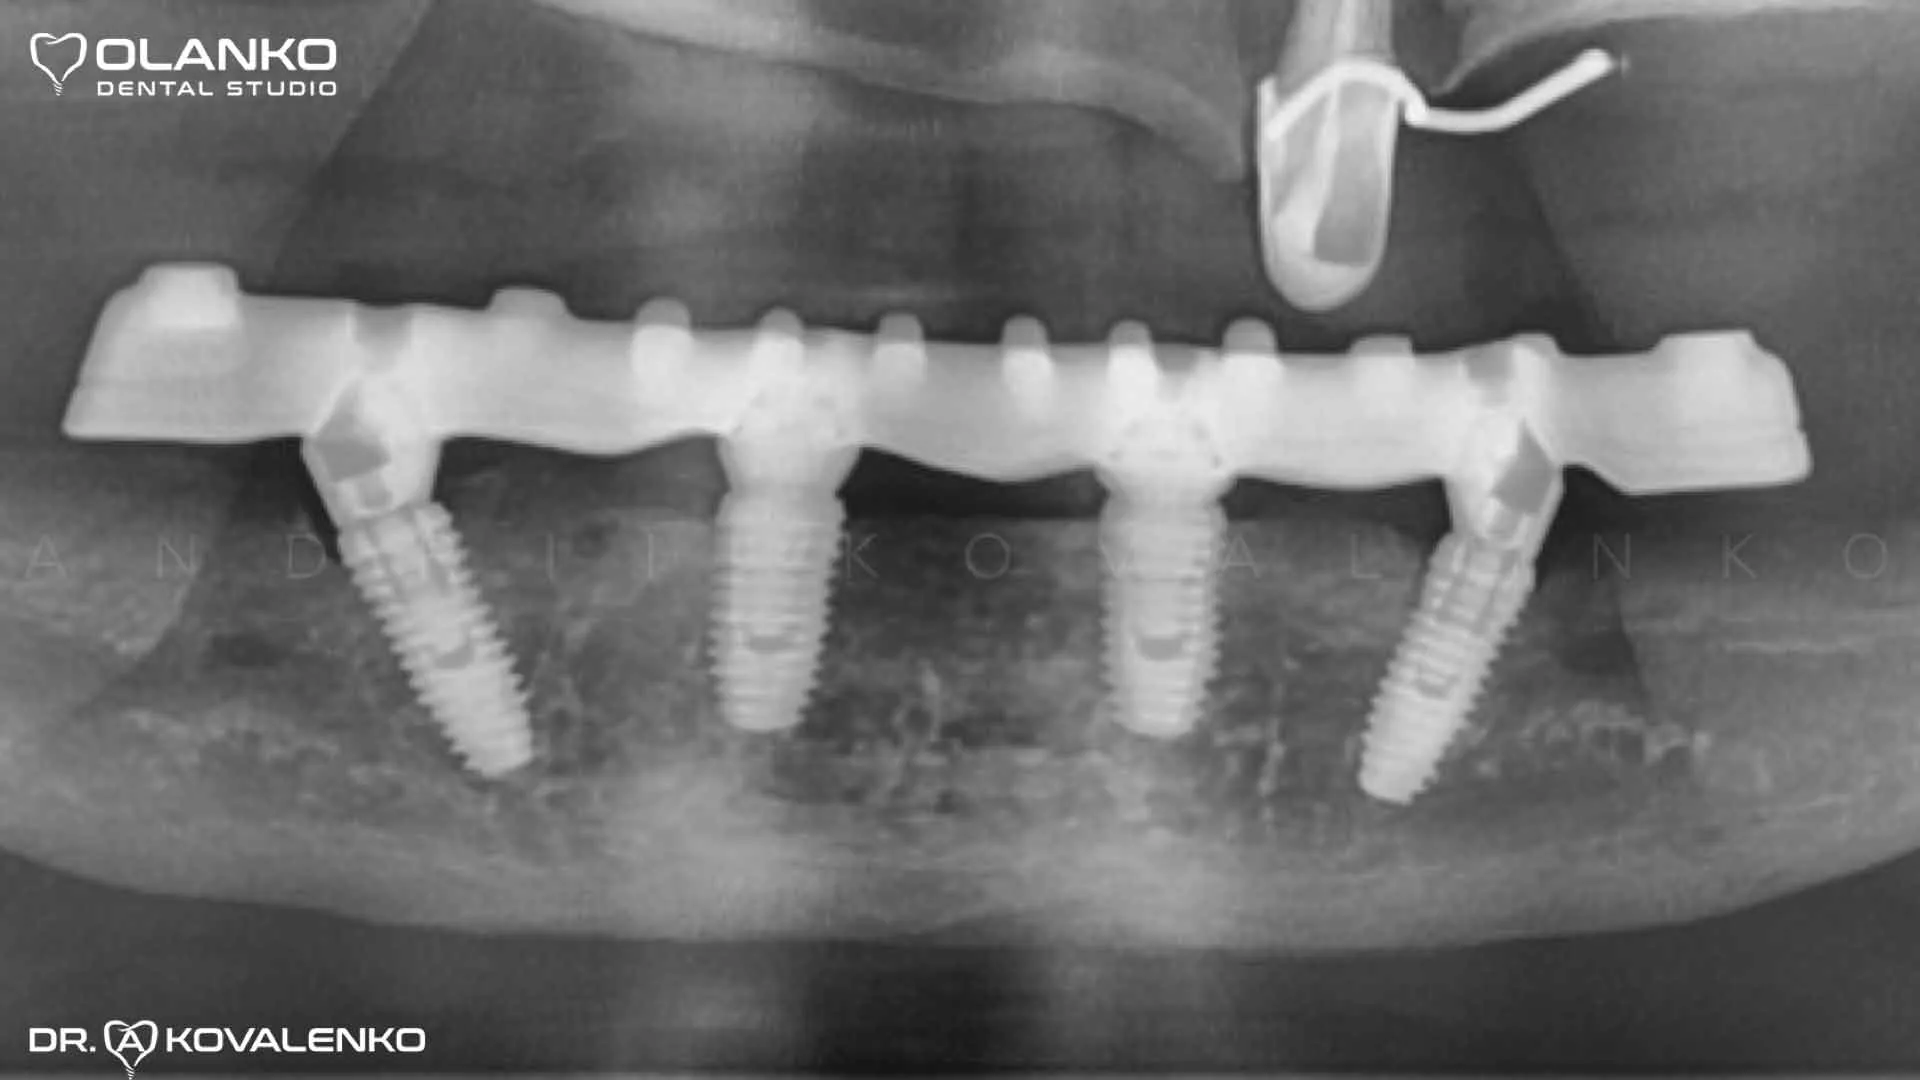

Приклад протезування по технології All on 4 беззубої нижньої щелепи

Ситуація до встановлення імплантів

Фото після установки та приживлення імплантів

Фото після установки зубного протеза з опорою на 4 імпланта